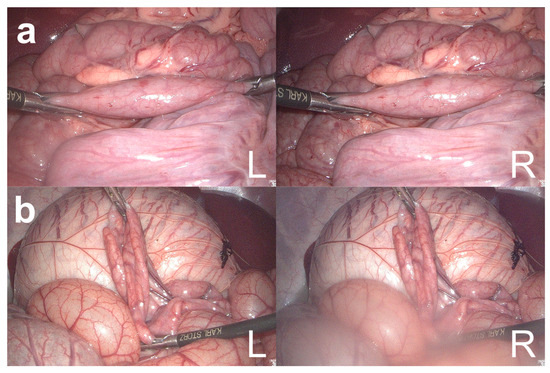

| 3. Bowel rotation | ||||

| 0° in x-plane | 68 | 100 ± 0 | 68 | 7.3 ± 36.2 |

| 45° in x-plane | 69 | 96.7 ± 20.5 | 66 | 4.1 ± 37.8 |

| 90° in x-plane | 70 | 100 ± 0 | 69 | −24 ± 24.3 |

| 135° in x-plane | 65 | 93.9 ± 24.2 | 61 | −13.1 ± 22.8 |

| 0° in y-plane | 64 | 84.4 ± 36.6 | 54 | 4 ± 21 |

| 45° in y-plane | 59 | 79.7 ± 40.6 | 47 | 15.8 ± 40.4 |